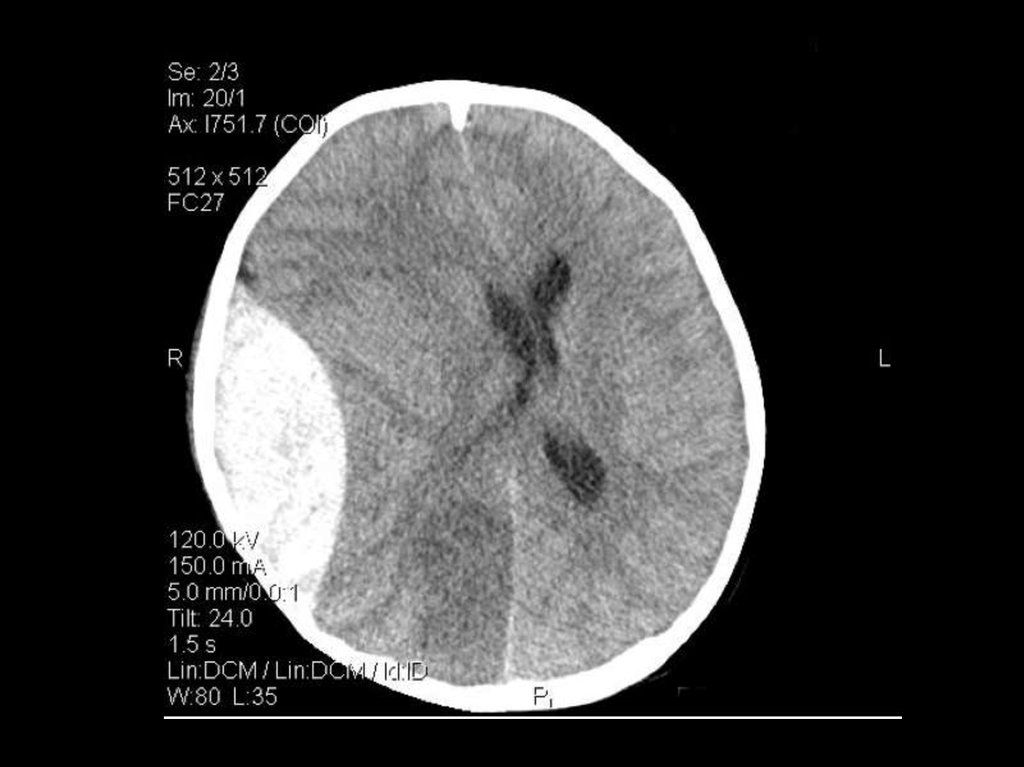

84-year-old man with a history of hypertension

Initial blood pressure of 230/120 mm Hg

12 hours after

brain death within 1 hour